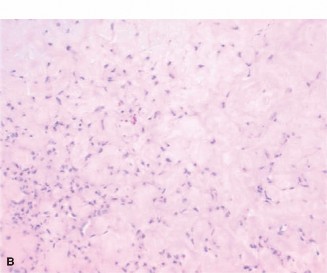

Histological analysis of the core biopsy specimens revealed a distinctly lobulated architecture. The lobules were composed of a biphasic population of cells set within a variably myxoid and chondroid background matrix. At the periphery of these lobules, there was increased cellularity consisting of spindle-shaped and stellate cells. The intervening stroma between the lobules was highly vascularized and fibrous, occasionally containing multinucleated giant cells.

Importantly, while mild cellular atypia and pleomorphism were noted—a common finding in chondromyxoid fibroma that can lead to misdiagnosis—there were no atypical mitotic figures, and no frank anaplasia or permeative growth patterns characteristic of malignancy were observed. The synthesis of the clinical, radiographic, and histopathological data definitively confirmed the diagnosis of a Chondromyxoid Fibroma.